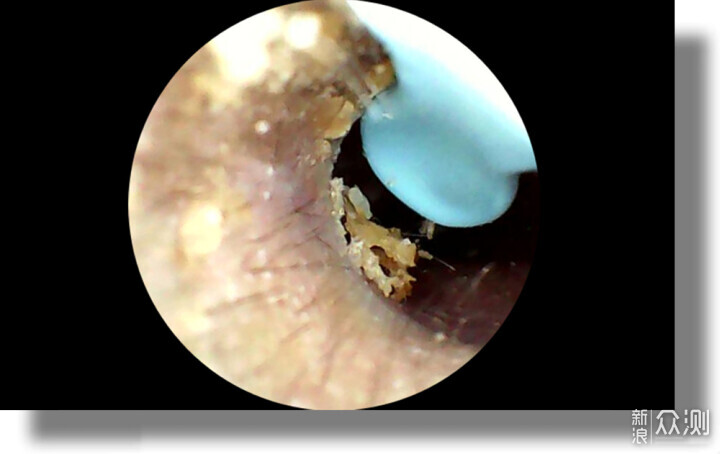

這款掏耳勺的鏡頭搭載了一枚1000萬像素高清內窺鏡,能夠實現醫療級的微距成像能力。配合鏡頭附近的6顆全向LED精密光學陣列,結合先進的OAS光透鏡技術,可以實現360°無陰影照明效果。

西聖Find智能可視耳勺憑藉自研的A-Zoom動態調焦技術與智能多軸陀螺儀,實現了毫秒級對焦與智能防抖,在實際的操作使用中可以看到,呈現的畫面圖像流暢無縫對焦,無論是細微的耳垢還是耳道的每一個角落,都能清晰的呈現在手機屏幕中。

為了保證畫面的流暢性,西聖Find智能可視耳勺特別採用了無人機上專用的Wi-Fi芯片,結合全速天線短陣3.0增強技術,實現最高30FPS的傳輸速率,確保了采耳過程中的視頻畫面不僅流暢而且穩定。在我在使用智能可視挖耳勺時,可以明顯感受到的實時性,在整個的采耳過程中,絲滑流暢流暢的很。